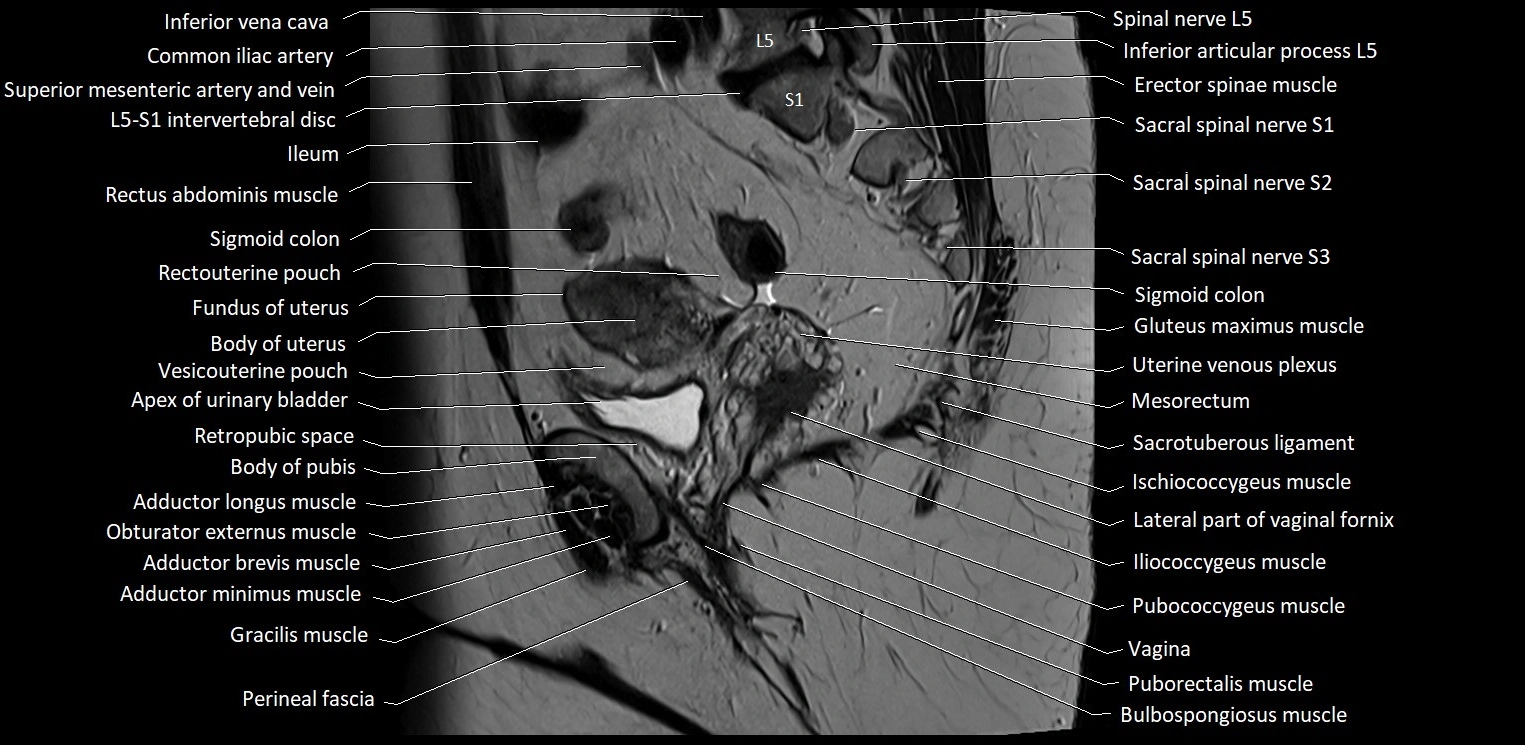

- Apex of urinary bladder

- Body of pubis

- Body of uterus

- Common iliac vein

- Fundus of uterus

- Gluteus maximus muscle

- Ileum

- Iliococcygeus muscle

- Inferior articular process of L5 vertebra

- Pubococcygeus muscle

- Puborectalis muscle

- Rectouterine pouch (pouch of Douglas)

- Rectum

- Retropubic space

- Sacrotuberous ligament

- Sigmoid colon

- Vagina

- Vesicouterine pouch